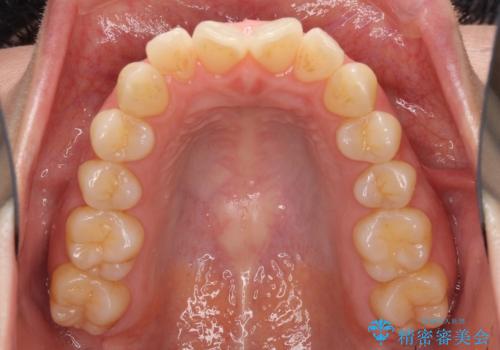

前歯の叢生とオープンバイト インビザラインでの矯正治療

- 前歯の開咬を気にして来院された患者様です。

開咬の治療は、前歯を閉じるように動かすとともに、上下臼歯を圧下(骨内にめり込ませる)させることで進めて行きます。

インビザラインは臼歯の圧下を効果的に行えるため、インビザラインを用いて矯正治療を行うこととしました。

オープンバイトは舌の突出癖により誘発され、治療後も突出癖が残っている容易に後戻りしてしまいます。

治療期間を短縮するためにも、舌突出癖の改善が極めて重要となります。